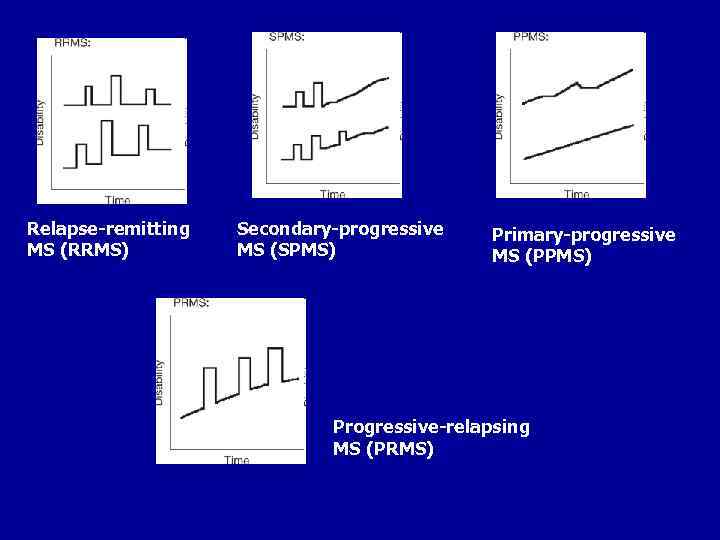

ОСОБЕННОСТИ ТЕЧЕНИЯ ЗАБОЛЕВАНИЯ Выделяют варианты течения PC. • Ремитирующее течение (relapsing-remitting) - включает две основные стадии: - обострение (экзацербация) - ухудшение имеющихся симптомов или появление новых после того, как состояние больного было стабильным не менее месяца; - ремиссия - полное или неполное восстановление функций и отсутствие нарастания симптомов. В начале заболевания 80 -85% больных имеют этот вариант PC. • Первично-прогрессирующее течение (primary-progressive) отмечается у 15 -20% больных и с самого начала характеризуется прогрессированием с временной стабилизацией или временным незначительным улучшением. Среди этих больных преобладают мужчины и больные старшего возраста. • Вторично-прогрессирующее течение (secondary-progressive) - первоначально ремиттирующее течение сменяется прогрессированием без ремиссий с кратковременными периодами стабилизации. Этот вариант наблюдается у 60% больных и рассматривается как этап развития ремиттирующей формы.

ОСОБЕННОСТИ ТЕЧЕНИЯ ЗАБОЛЕВАНИЯ • Прогрессирующе-ремиттирующее течение (progressive- relapsing) - встречается примерно у 6% больных и характеризуется прогрессированием с самого начала болезни, на фоне которого в дальнейшем возникают обострения (между обострениями продолжается прогрессирование заболевания). Помимо этого выделяют также: • - доброкачественный вариант течения заболевания, при котором на протяжении более 10 лет больной имеет незначительные нарушения функций - не более 1 -2 баллов по шкале EDSS • - злокачественный вариант с быстрым прогрессированием, приводящим в течение 5 лет к значительной инвалидизации - более 6 баллов по шкале EDSS. • Определить вариант течения болезни в 20 -30% случаев достаточно сложно. Более благоприятен прогноз у лиц молодого возраста, женского пола, при начале заболевания с ретробульбарного неврита или нарушений чувствительности.

Relapse-remitting MS (RRMS) Secondary-progressive MS (SPMS) Primary-progressive MS (PPMS) Progressive-relapsing MS (PRMS)